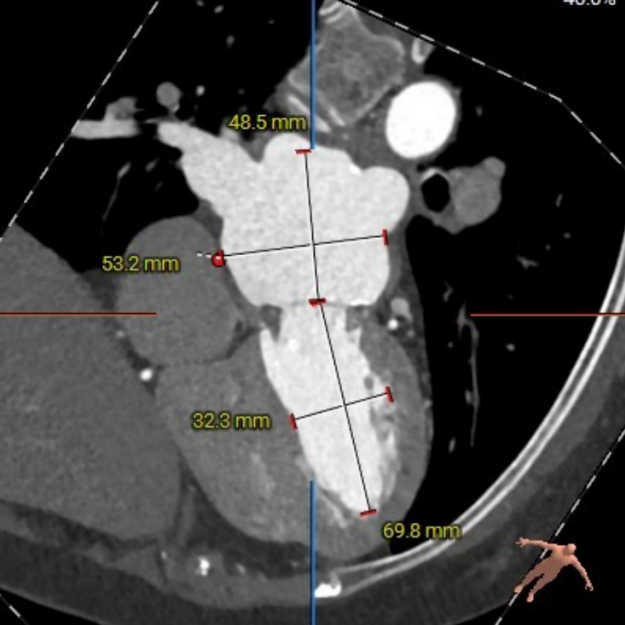

二尖瓣生物瓣架内径23mm,外径25mm,根据瓣架形态,符合25#Mosaic瓣膜

模拟23#Renatus植入

模拟25#Renatus植入

NEO-LVOT面积293.6mm²,新流出道梗阻风险低

左房53×48mm,靠后下的房间隔穿刺点距二尖瓣高度17.9mm。患者房间隔显著增厚、钙化,房间隔穿刺点较低,考虑房间隔穿刺及器械到位较为困难。